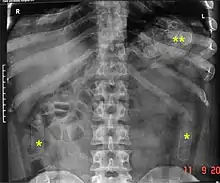

Распространённым способом скрытного транзита наркотиков через границы является его провоз в телах наркокурьеров, в том числе в желудке и кишечнике, особенно при использовании авиалиний и перевозке наиболее дорогих на единицу массы веществ (героин, кокаин)[2]. Формируются небольшие пакеты (несколько граммов), упакованные в герметичную тару, например презервативы, которые затем проглатываются. Курьер может везти до десятков таких пакетов. Если пакет разрывается или теряет герметичность, курьер, как правило, погибает от передозировки наркотика[4]. Через 2—3 суток пакеты выходят естественным путём вместе с калом. В случае необходимости быстрого извлечения пакетов курьеру дается сильное слабительное.